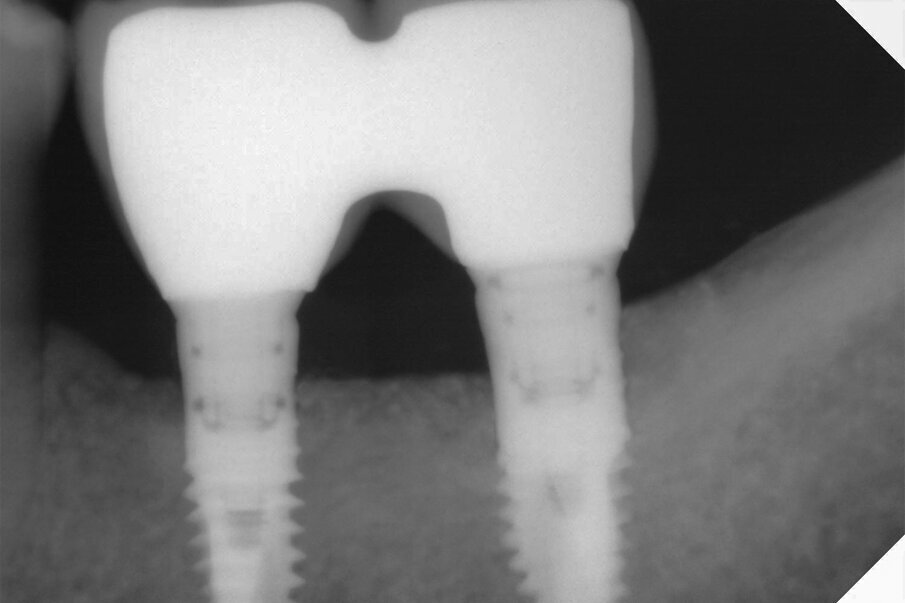

Il caso in esame riguarda una paziente di 53 anni, fumatrice, che si presentava all’osservazione per il consueto controllo periodico lamentando sanguinamento e dolore gengivale durante le manovre di igiene orale a livello di due impianti situati in posizione 4.6 e 4.7. A seguito dell’esecuzione di una CBCT per altri motivi si è potuto evidenziare un marcato riassorbimento osseo perimplantare (Fig. 1). Come si può osservare durante la chirurgia (Fig. 3) l’esposizione della superficie implantare è superiore al 50%. In entrambe le fixture con un maggior coinvolgimento in posizione 4.6. È stata inoltre riscontrata una sofferenza della mucosa attorno ai monconi delle due fixture.

Fig. 1 - CBCT in sezione laterale. I coni di riassorbimento coinvolgono un’ampia porzione della superficie implantare.